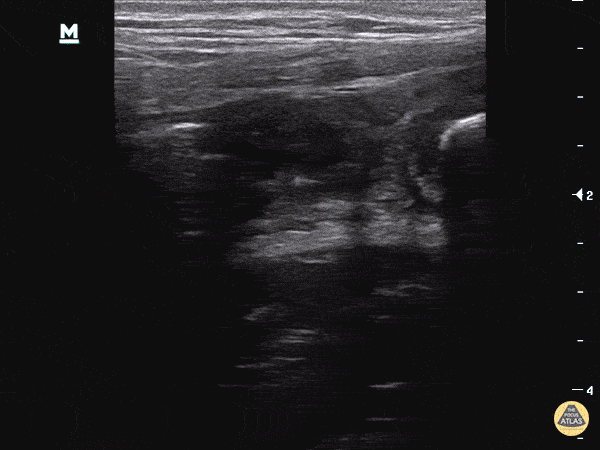

Patient with RLQ pain, ttp, fever and guarding. POCUS performed at area of maximal tenderness demonstrating a dilated appendix >6mm with a blind distal end and sonographic McBurney's. Two fecaliths can be visualized, one at the distal end and a smaller one more proximally (right side of the screen). Dr. Sathya Subramaniam - Children's Hospital of Philadelphia